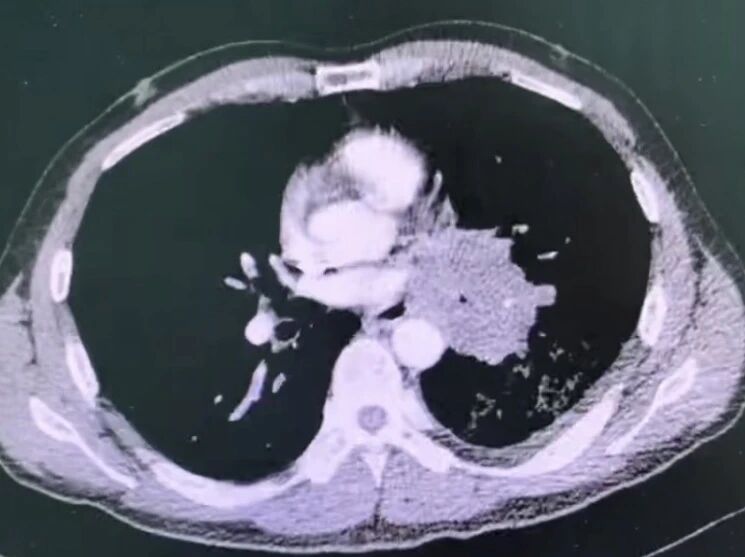

1775811334299774.jpg

胸部ct提示左肺门巨大占位,包绕肺门主要结构